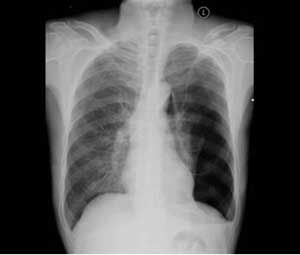

1、由於肋軟骨在X線片中不能顯影,胸部X線檢查不能發現病變徵像,但有助排除胸內病變、胸壁結核、肋骨骨髓炎。